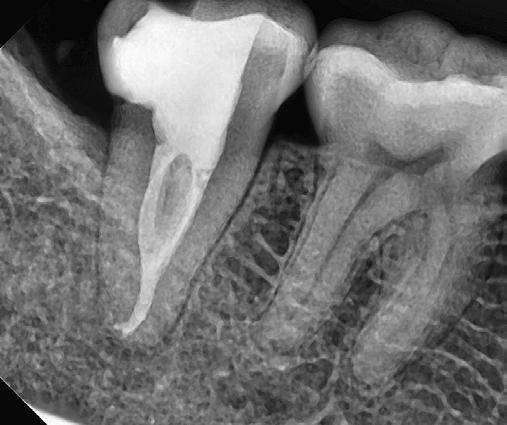

10. ábra: A periapikális felvételen egyértelműen megmutatkozik a 46-os és 47-es fogak között kialakult csontos defektus, valamint a gyökereket fedő parodontális rostok károsodása. – 11. ábra: A disztális gyökér amputációját követően a csonthiány kiterjedése látszólag tovább növekedett. – 12. ábra: A 22 évvel később készített kontrollfelvételen jól megfigyelhető a csontos defektus telődése, valamint új kortikális csontállomány kialakulása.

Gyökéramputációt főként a furkáció érintett nagyőrlő fogak ellátása során szoktunk alkalmazni. Derks és mtsai. vizsgálatában a gyökéramputált nagyőrlő fogak közel 80%-a 20 évvel a beavatkozás elvégzését követően is megtartott volt. 1998 októberében egy 39 éves férfi páciens a jobb alsó kvadránsban jelentkező ínyérzékenység miatt kereste fel rendelőnket. A klinikai vizsgálat során jobb alsó első és második nagyőrlő fog között (46–47) nagy kiterjedésű csontveszteséget észleltünk. Ettől eltekintve a teljes fogazat parodontális státusza megfelelőnek bizonyult. A jobb alsó kvadránsban végzett szenzibilitás vizsgálat során arra az eredménye jutottunk, hogy a 46-os fog vélelmezhetően elhalt (10. ábra).

A páciens beleegyezését követően a 46-os fog disztális gyökere, a disztális gyökér felett lévő koronális rész megőrzése mellett rezekcióra került (11. ábra). A rezekciót követően a referáló orvos a 46. és 47. fogak koronáját Ribbond szalag és kompozit segítségével egymáshoz rögzítette. A sebészi beavatkozást követően 22 évvel készült kontrollfelvételen a lézió csontos telődése, kortikális csontállomány kialakulása, valamint a furkáció körüli csontos regeneráció volt megfigyelhető (12. ábra) A károsodott fogak megtartására szolgáló lehetőségek fejlődésének, valamint az implantátumok behelyezésével kapcsolatos rizikófaktorok jobb megértésének köszönhetően ma már más szemmel vizsgáljuk a fogak eltávolításának szükségességét. A kérdéses prognózissal vagy a kis protetikai értékkel rendelkező fogak eltávolítása előtt mindig érdemes felmérni az ezzel elérhető lehetséges előnyök nagyságát. A kemény- és lágyszöveti pótlás lehetőségeinek fejlődésével, a PRF elérhetőségével, a minimálinvazív sebészeti módszerek és az operációs mikroszkópok elterjedésével, valamint a varróanyagok és varrat technikák egyre kifinomultabbá válásával ma már alaposan el kell gondolkodnunk az előtt, hogy egy fogat egy implantátum behelyezése érdekében eltávolítsunk. Mára sokkal kedvezőbb prognózist és sokkal nagyobb sikerességet tudunk elérni a korábban menthetetlennek gondolt fogak kezelése során.